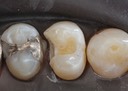

Mark Chun #13,14,15 pre-op

Mark Chun #13,14,15 amalgam removal

Mark Chun #13,14,15 prep